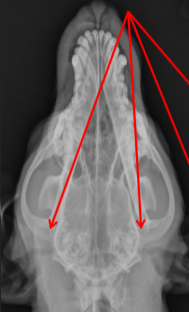

Temporomandibular Joint

ID radiographic view

VD